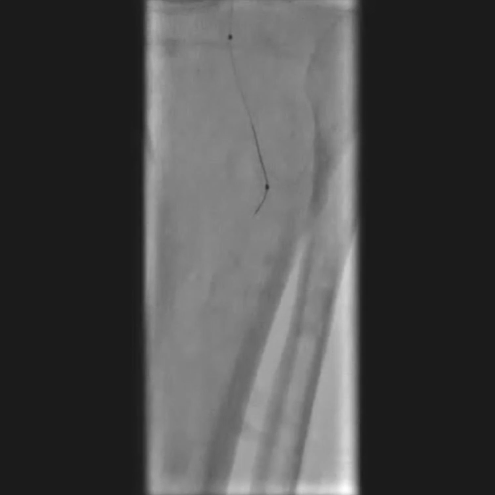

先尝试顺行穿刺,导丝进入内膜下未能成功通过;改为逆行穿刺胫后动脉,导入V18导丝,采用Safari技术(逆行导丝通过闭塞段与近端导管对接)建立工作轨道。

2

球囊预扩张与病变处理